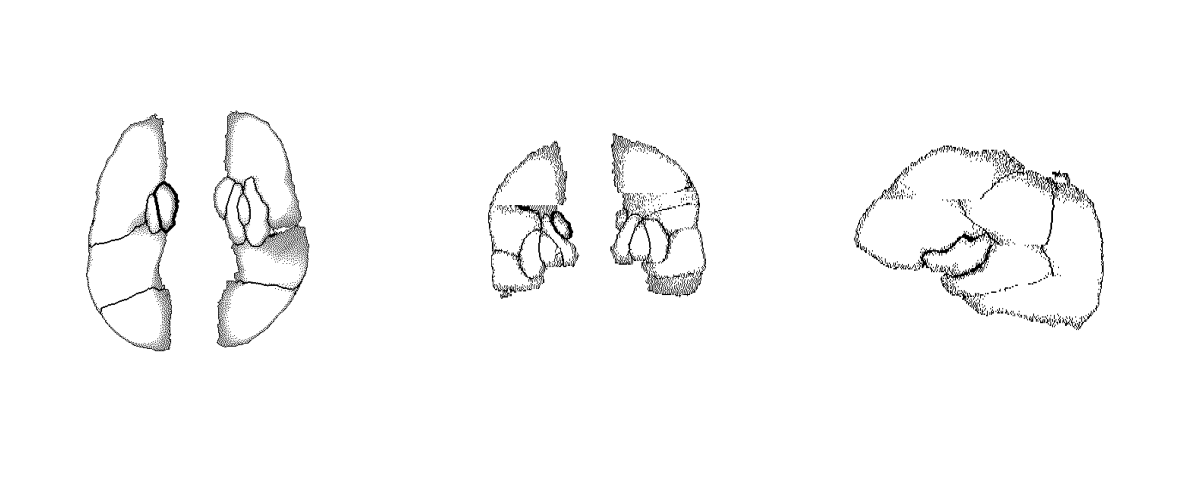

The definitive method adopted to ensure a consistent and universally reliable translation of overlay point clouds into filled segmentation masks specific to the ASPECTS region involved employing a sophisticated approach characterized by atlas-based registration using an aggressive variant of Symmetric Diffeomorphic Normalization (SyN) as described in the next section. In essence, the principal objective was to utilize a publicly available standardized brain template, referred to as an atlas, to systematically register all computed tomography (CT) scans containing point cloud overlays with said atlas. This registration process was followed by applying the resultant transformations to the overlays themselves in order to align them within a similar spatial domain, achieving maximum consistency across subjects. The registered and transformed overlays were subsequently integrated to construct a unified volumetric data set. All registered overlays were then used to generate a single volume, where each overlay was aggregated into a single mean overlay template.

Despite the aggregation of all overlays it was still not trivial to get a proper segmentation mask for the aggregated overlay using morphological operations. Therefore a 3D segmentation tool was used to manually annotate such a segmentation mask for the aggregated overlays, which resulted in a single, manually annotated, segmentation mask, that could be used as an atlas as well. Ultimately the process to get robust segmentation masks for each individual scan, containing ASPECTS region overlays (point clouds) was as following:

Below, the predicted ASPECTS regions of a validation sample on a single slice and the entire predicted volume is visualized.